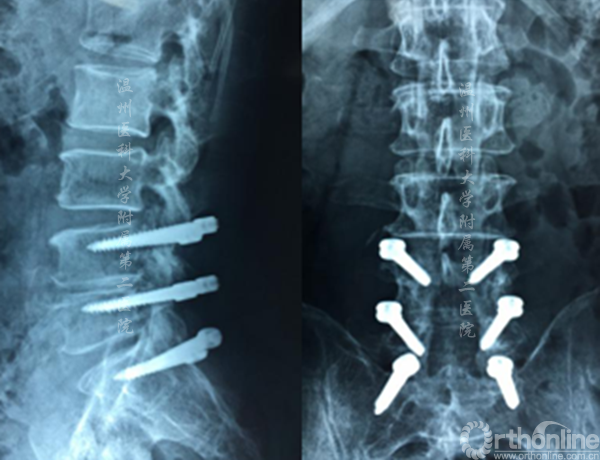

案例2

腰3/4,腰4/5椎间盘突出伴椎管狭窄,行双节段CBT螺钉固定。

左图:提示腰3/4椎管狭窄 右图:提示腰4/5椎管狭窄

术后X线显示CBT螺钉未松脱、断裂,螺钉位置良好